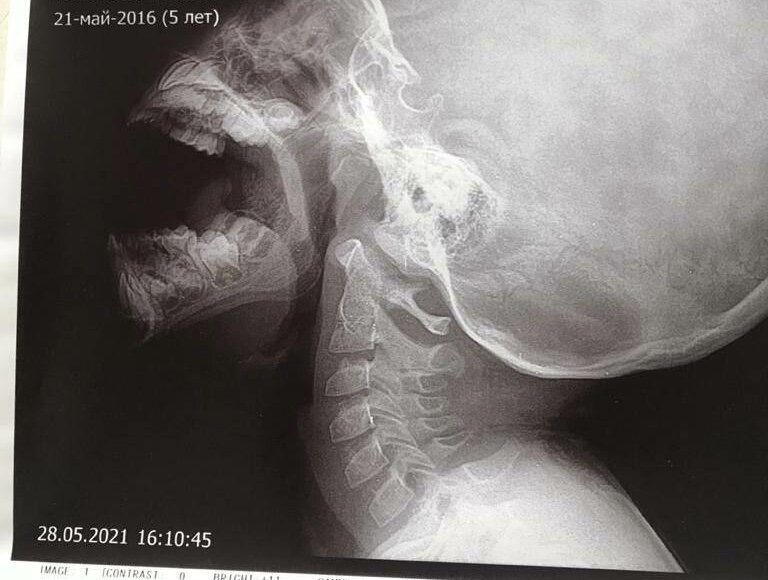

В марте 2020г ЛОР врачом был выставлен диагноз: Гипертрофия #миндалин 2 ст., #Аденоиды 2 ст. Ребенок в течение года получал системную коррекцию состояния здоровья продуктами Кораллового клуба.

Результат оказался «бомбовский» - ребенку была запланирована #операция, которую просто отменили из-за отсутствия показаний.

При очередном осмотре 01.06.2021г врачом сурдологом-отоларингологом г. Краснодара заключение: Слух в норме. Аденоиды 1-й степени. Подтверждено R-логическими снимками.